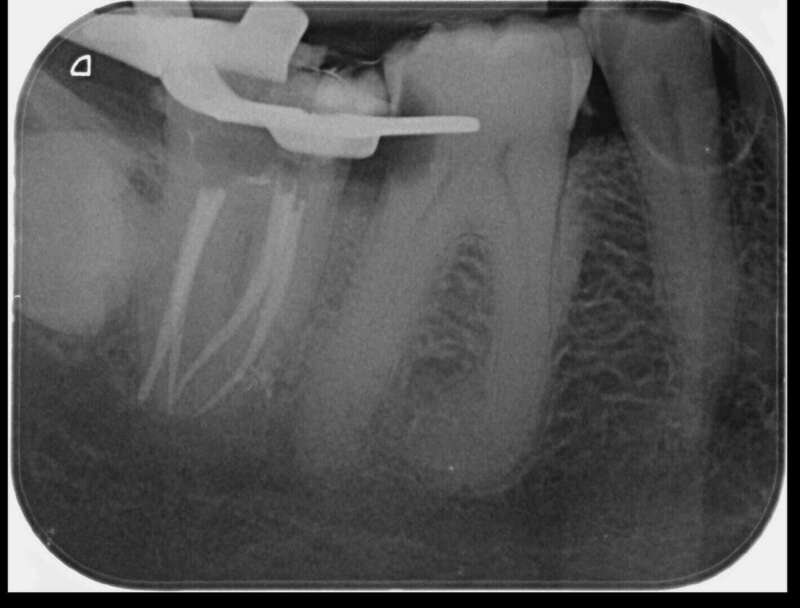

Avant

Après